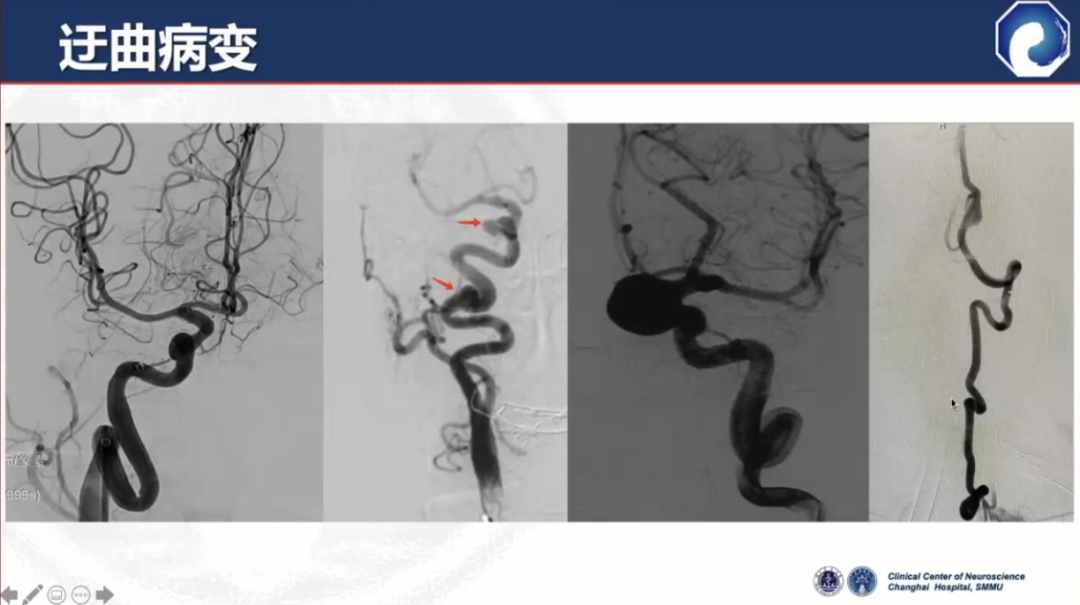

在迂曲血管中通过性能较差

通桥医疗银蛇®DA在迂曲血管中也能实现高到位